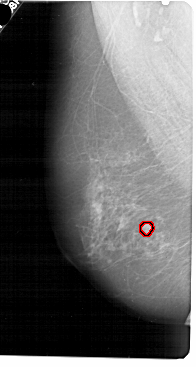

A_1853_1.RIGHT_MLO

RIGHT_CC LINES 5206 PIXELS_PER_LINE 2416 BITS_PER_PIXEL 12 RESOLUTION 43.5 NON_OVERLAY

RIGHT_MLO LINES 5461 PIXELS_PER_LINE 2491 BITS_PER_PIXEL 12 RESOLUTION 43.5 NON_OVERLAY